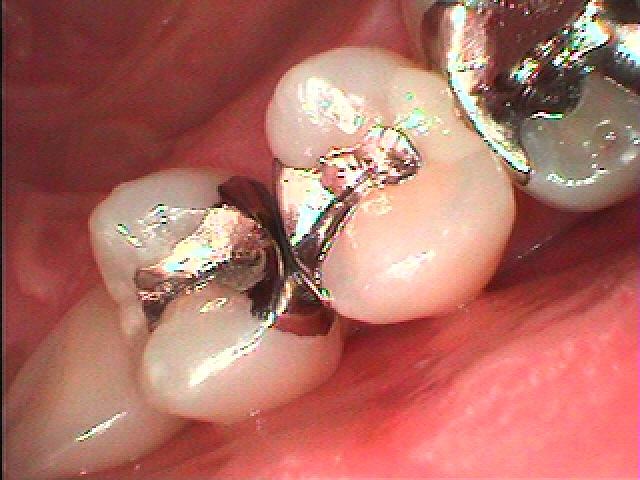

銀歯、詰めてある樹脂を外すと中が虫歯になっていました

虫歯を除去してCR樹脂にて覆罩を行っています